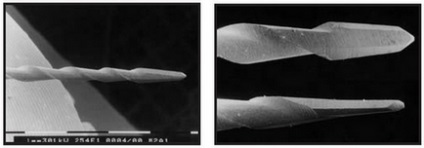

Ábra. 2. Base Mtwo eszközkészlet egy hosszúkás működő része 21 mm-es, eltávolítására dentin túlnyúló széleit a szájban a csatorna és a falon a hozzáférési üreg.

Keresztmetszetben úgy néz ki, Mtwo Latin S betű két vágóéllel. (Ábra. 3).

Ábra. 3. A keresztmetszet a szerszám Mtwo (SEM). A felületek a két vágópenge alkot latin betűvel